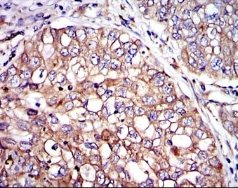

CRK Mouse Monoclonal antibody[3GPO1]

This gene encodes a member of an adapter protein family that binds to several tyrosine-phosphorylated proteins. The product of this gene has several SH2 and SH3 domains (src-homology domains) and is involved in several signaling pathways, recruiting cytoplasmic proteins in the vicinity of tyrosine kinase through SH2-phosphotyrosine interaction. The N-terminal SH2 domain of this protein functions as a positive regulator of transformation whereas the C-terminal SH3 domain functions as a negative regulator of transformation. Two alternative transcripts encoding different isoforms with distinct biological activity have been described.

Immunogen :   Purified recombinant fragment of human CRK expressed in E. Coli.

IHC    1/200 - 1/1000